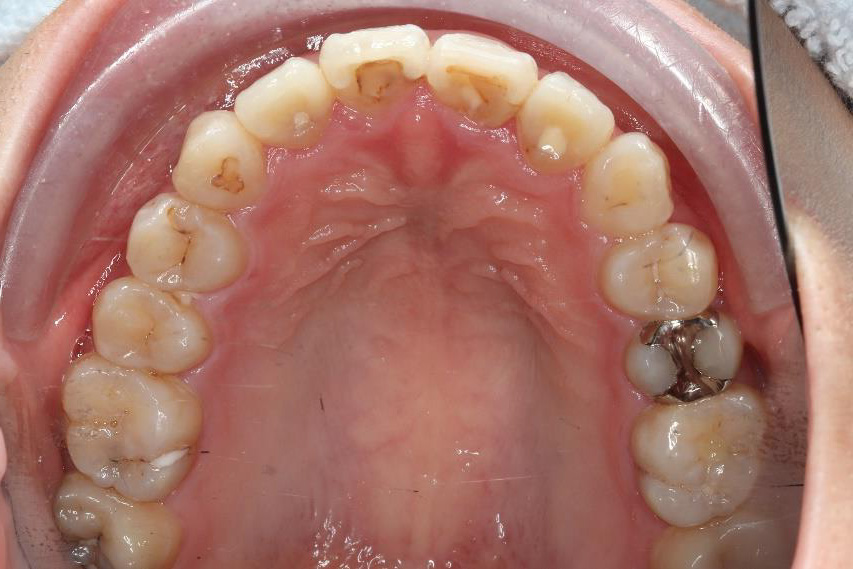

乱ぐい歯、でこぼこがとても酷い状態になります。歯が前後的に重なってしまっている、八重歯になっているなどがこのジャンルに入ります。

顎の大きさと歯の大きさのギャップが大きく、時には歯を抜かないと矯正治療ができない場合もあります。当院では治療期間が長くなるが抜かない治療方針など、一つの治療プランだけでなく、さまざまな可能性の治療方針を説明させて頂くよう心掛けております。こういった考え方はインフォームド・チョイスと言われ近年大切にされている考え方と言われております。

治療前

治療終了前